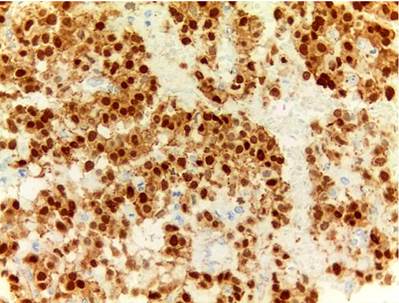

En cuanto a las características morfológicas consideradas como predictoras de comportamiento agresivo, la invasión de la cápsula fue la más común, presente en 6 (37 %) de los casos; solo uno de ellos presentó adicionalmente invasión linfovascular y perineural en un paciente pediátrico de sexo masculino. Todos los casos presentaron hemorragia o necrosis. En cuanto a los marcadores de inmunohistoquímica, todos los casos (100 %) presentaron positividad nuclear para β-catenina, otros marcadores positivos fueron los antígenos CD10 y CD56 en un 43 % del total de casos y los receptores de progesterona fueron positivos en el 100% de los casos a los que se le realizó dicho marcador, que corresponden al 25 % del total de casos; la sinaptofisina fue positiva en 4 casos, que corresponden al 25 % del total de casos y al 50 % de casos en los que se realizó; la cromogranina y el C-kit fueron negativos en todos los casos. Solo tres casos tuvieron el panel de inmunohistoquímica completo (β-catenina, CD10, receptores de progesterona, C-kit, sinaptofisina y cromogranina). La positividad de los marcadores previamente expuestos se correlaciona fuertemente con lo descrito en la literatura.

En cuanto a los marcadores de inmunohistoquímica, son característicamente positivos la β-catenina y los receptores de progesterona en el 100 % de los casos. Son positivos para CD56 en el 98 %, la sinaptofisina puede alcanzar una positividad focal de hasta 62 %, mientras que la cromogranina es positiva solo en el 13 % de los casos, el CD10 en el 93 % de los casos, el C-kit en el 81 % y la ciclina D1 en el 71 %, mientras que la E-cadherina es positiva solo en el 13 % de los casos; las citoqueratinas pueden ser positivas en el 30 % al 70 %. La inhibina, antígeno carbohidrato 19-9 (CA 19-9), mucina 6 (MUC6), proteína caudal homeobox 2 (CDX2), factor 4 de transcripción de unión a octámeros (OCT4) y el antígeno CD30 son negativos1,4,8,15,16.